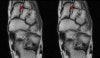

3. Posterior Talofibular ligament

Coronal (left) and axial (right) T1W images assessing the normal posterior talofibular ligament. This ligament is normally less dark than the anterior talofibular ligament.